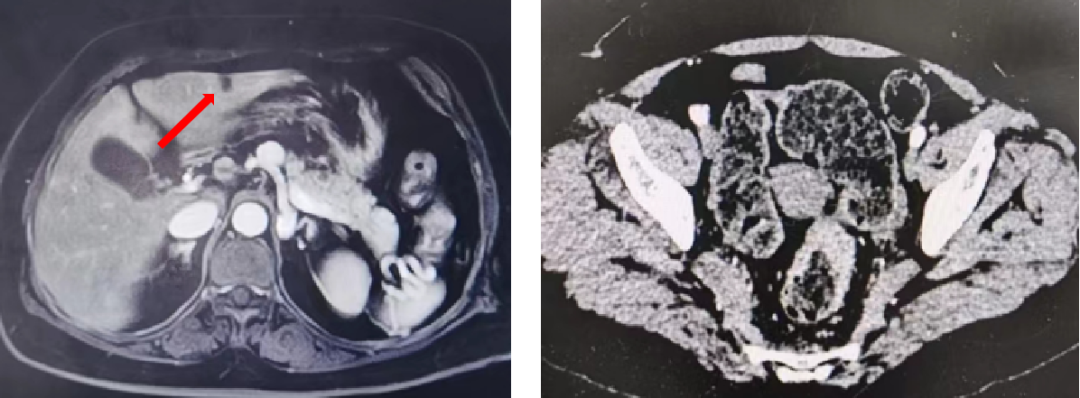

2021-09-25 复查CEA:82.1ng/ml。

胸部增强CT:双肺多发转移瘤,部分较前片增大;直肠壁增厚,较前稍减小;肝左叶低密度影,较前片变化不大。

肺内靶病灶稳定,出现新病灶,疗效评估PD。

2021-12-13 复查 CEA:165.9ng/ml。

胸部+全腹部增强CT:直肠壁增厚,较前未变化;肝左叶低密度影,较前片未变化;双肺多发转移瘤(靶病灶及非靶病灶增大)。

结肠镜:直肠距肛缘10-15cm见溃疡状新生物,侵及管腔多半周,边缘隆起,质脆、易出血,取检。病理:腺上皮高级别上皮内瘤变,灶性癌变。

疗效评估PD。